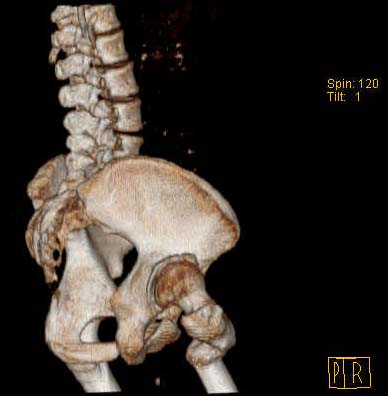

Уважаемые коллеги!Женщина, 35 летВ прошлом по поводу врожденного вывиха бедра перенесла операцию остеотомии по Шанцу

с удлинением правой ноги за счет бедра на уровне диафиза. В последнее время прогрессируют боли в правом тазобедренном суставе, порочное положение правой ноги, затруднена ходьба.Вопросы:1) Целесообразно ли эндопротезирование правого тазобедренного сустава?2) Целесообразный ли следующие действия: канал бедренной кости предполагаем вскрыть для введения ножки протеза на высоте угловой деформации, предполагаем низведение большого вертела с мышцами; протез будет подобран индивидуально, предполагается умеренная версия?В приложении рентгенограммы и трехмерная КТ.В цветном и более качественном варианте КТ размещена здесь